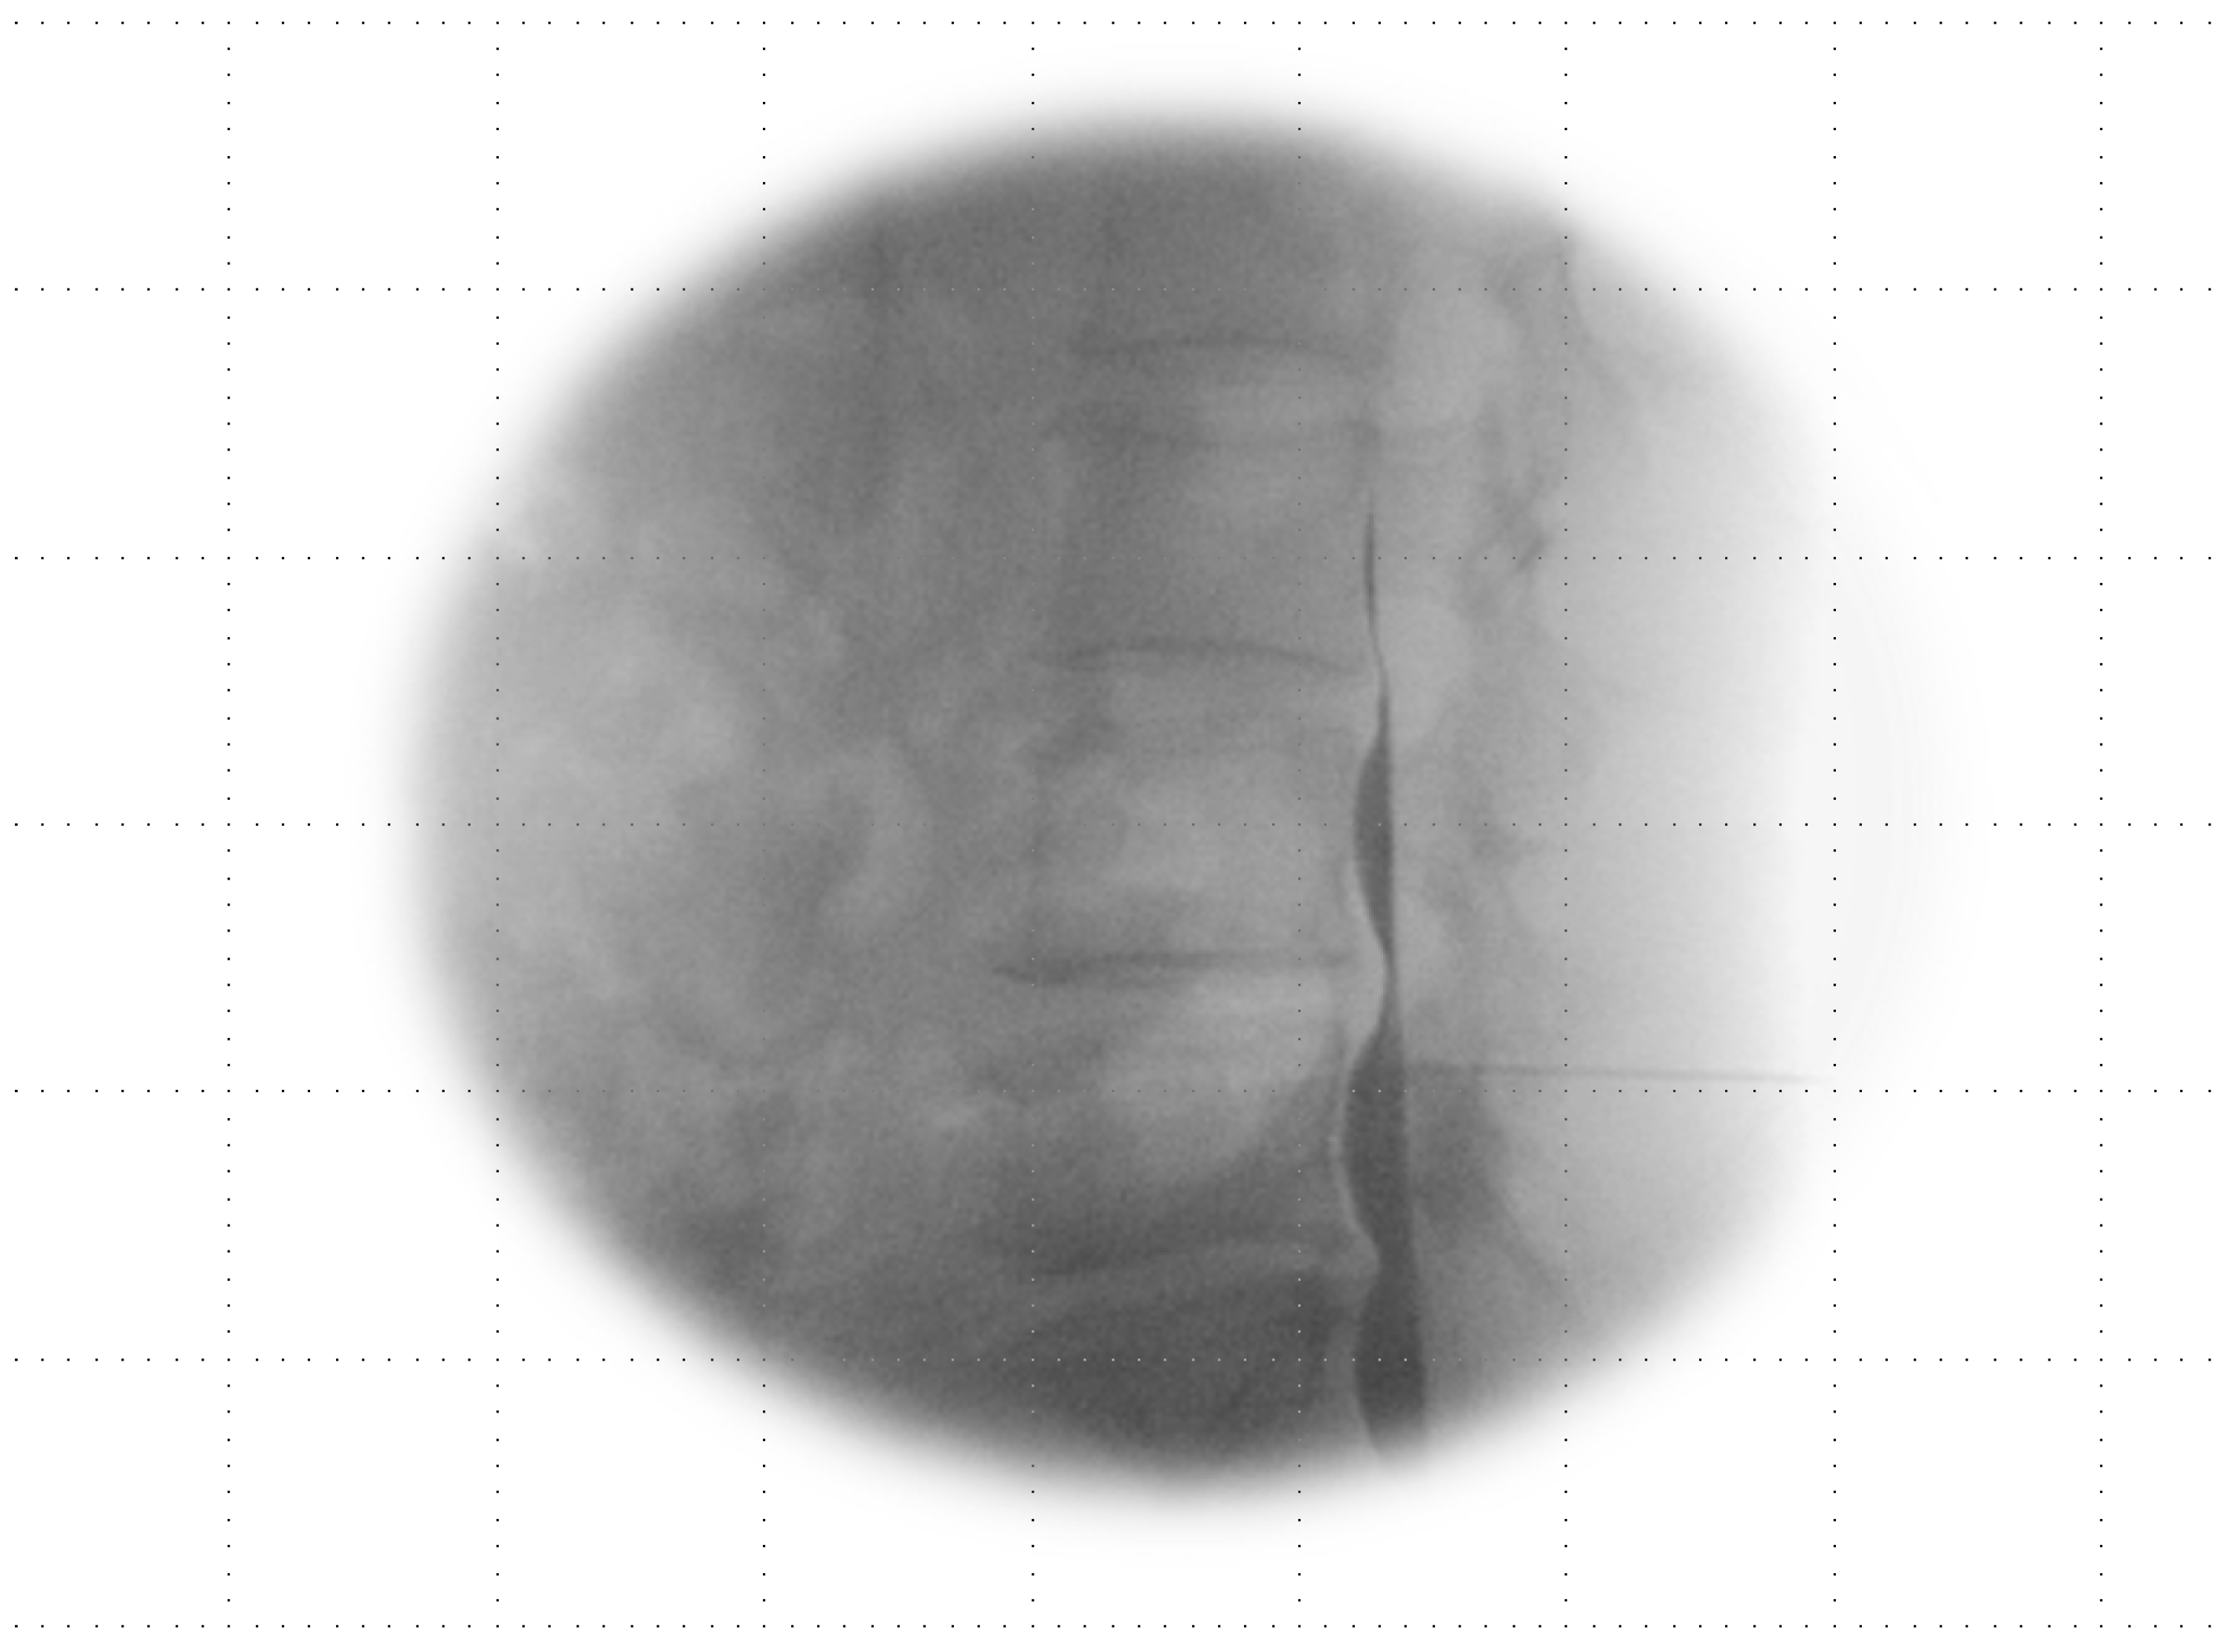

Anesthetics were administered if the Tuohy needle tip was situated within the epidural or subdural space (Figure 1A,B) or straddled between both spaces (Figure 2A,B).

Figure 2.

Combined epidural–subdural image. (A) AP view: imaging shows a thick, sausage-like mass of subdural contrast that transitions into a less dense epidural radiopaque image along the exiting nerve root, with the flow observed moving cranially. (B) Lateral view: the imaging reveals a progression from two thickened anterior–posterior columns positioned medially in the lower region (black arrow), transitioning to thinner, more peripheral anterior–posterior tracts (open arrow) that become more apparent in the epidural image as they flow cranially.